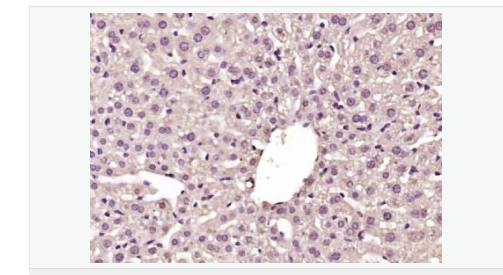

| 產品應用 | WB=1:500-2000 ELISA=1:5000-10000 IHC-P=1:100-500 IHC-F=1:100-500 IF=1:100-500 (石蠟切片需做抗原修復) not yet tested in other applications. optimal dilutions/concentrations should be determined by the end user. |

| 產品介紹 | GCKR is a subfamily member of the SIS (Sugar ISomerase) family of proteins. It is a regulatory protein that inhibits glucokinase in liver and pancreatic islet cells by binding non-covalently to form an inactive complex with the enzyme. This gene is considered a susceptibility gene candidate for a form of maturity-onset diabetes of the young. Function: Inhibits glucokinase by forming an inactive complex with this enzyme. Tissue Specificity: Found in liver and pancreas. Not detected in muscle, brain, heart, thymus, intestine, uterus, adipose tissue, kidney, adrenal, lung or spleen. Similarity: Belongs to the GCKR family. Contains 2 SIS domains. SWISS: Q14397 Gene ID: 2646 Database links: UniProtKB/Swiss-Prot: Q14397.6 Important Note: This product as supplied is intended for research use only, not for use in human, therapeutic or diagnostic applications. |